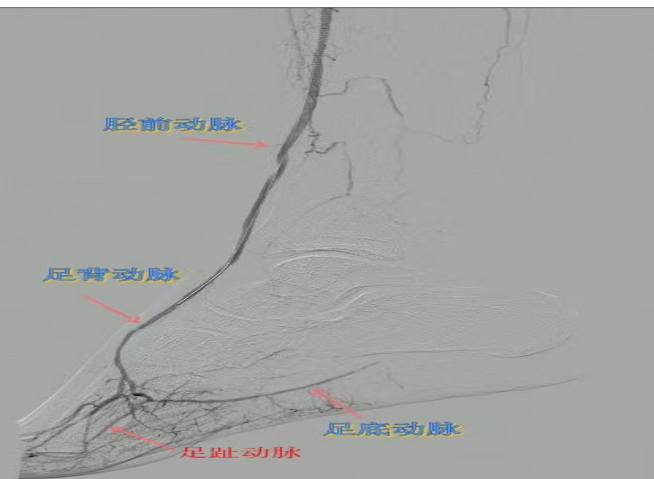

67歲女性患者,多年糖尿病、冠心病史,因右足潰爛伴涼麻疼痛長(zhǎng)達(dá)2年就診,此前曾接受外院介入術(shù)后血管再度閉塞。此次檢查發(fā)現(xiàn)其股淺動(dòng)脈、腘動(dòng)脈至膝下血管全程閉塞,且伴有嚴(yán)重鈣化。團(tuán)隊(duì)迎難而上,創(chuàng)新性經(jīng)足背動(dòng)脈逆向穿刺,耗時(shí)3小時(shí)成功貫通脛前動(dòng)脈。術(shù)后當(dāng)夜患者足部即感回暖,潰爛足趾疼痛顯著緩解。術(shù)后結(jié)合中藥外治(換藥、熏洗、去腐生肌膏外敷)加速創(chuàng)面愈合。該患者已于出院,院外換藥治療。

影像檢查:股淺動(dòng)脈、腘動(dòng)脈至膝下血管全程閉塞伴嚴(yán)重鈣化。